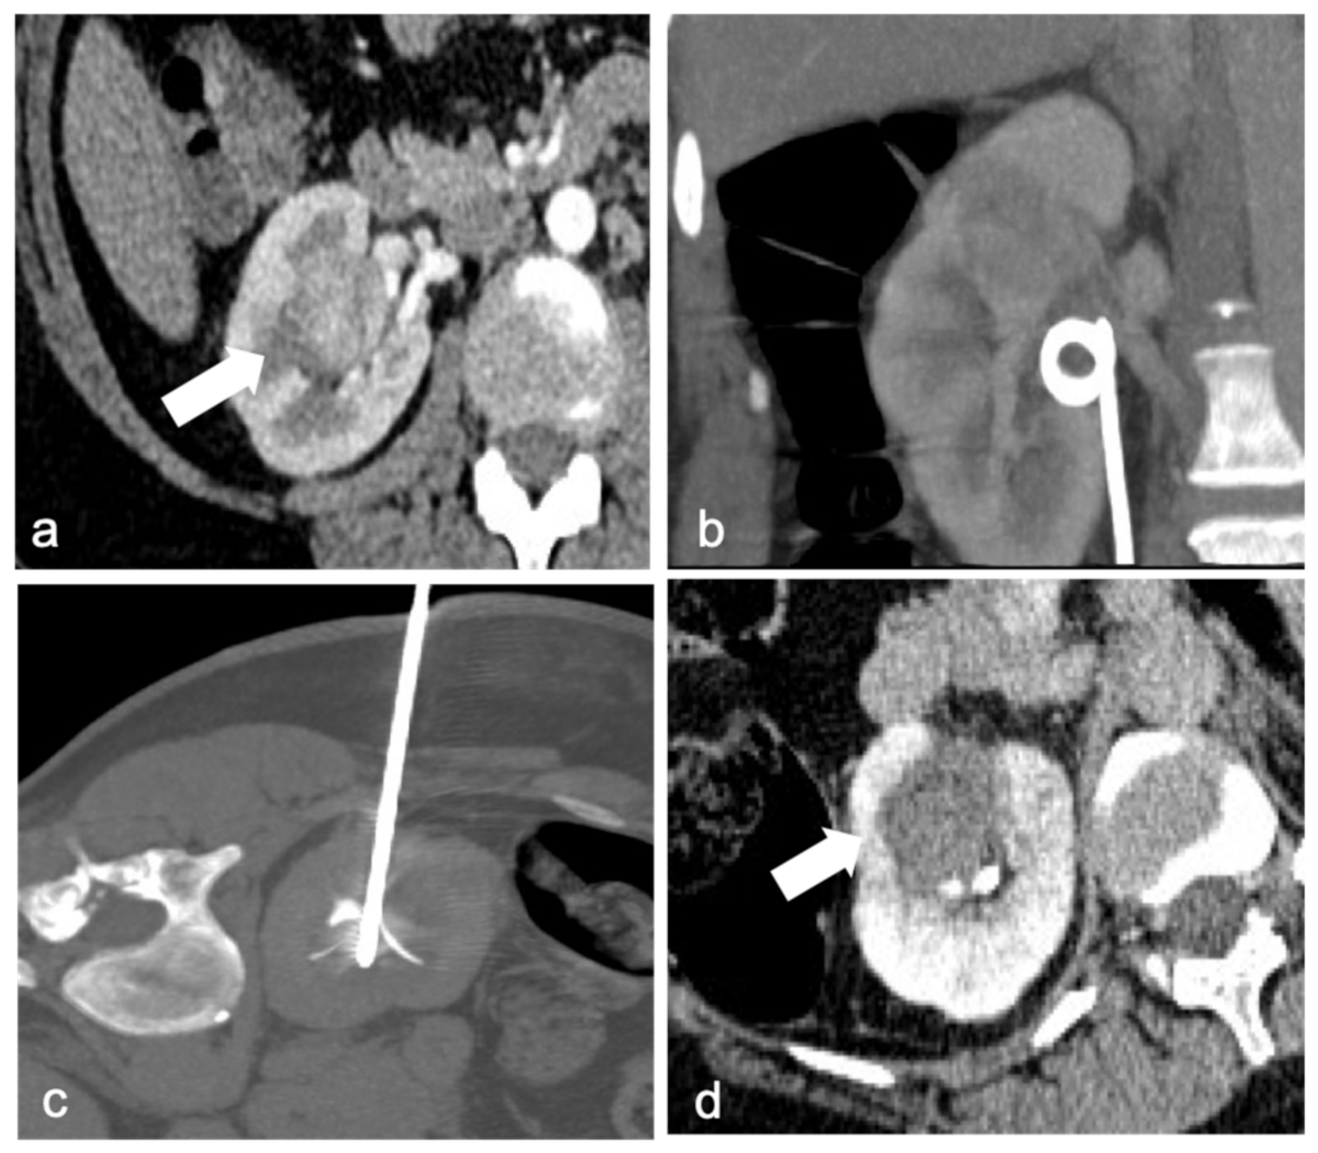

An important characteristic of RFA is the heat sink effect, generally known as a limit of this technique because the generated heat tends to decrease near structures with continuous liquid flow (large blood vessels ≥3 mm in diameter). This intrinsic feature can be useful to ablate perihilar tumors since it decreases the risk of damaging important anatomical structures with the high temperature. In addition, heat has an intrinsic coagulative effect, thus reducing the risk of minor hemorrhage [36]. Collecting system damage can occur as well, so it has been suggested placing a double J catheter in the ureter before the procedure in order to cool the collecting system (Figure 1). During the procedure, refrigerated water flows into the renal pelvis, protecting it from the heat [37].

Figure 1.

A 41-year-old woman with a biopsy-proven perihilar renal cell carcinoma of the right kidney ((a), arrow). Ureteral double-J stent was positioned right before the procedure to protect the pelvis and urinary tract with continuous refrigerated water flow (b). Precise positioning of the multi-tined RF probe in the right renal hilum mass (c). Contrast-enhanced CT after ablation shows the necrotic area (arrow), without any residual disease or immediate complication (d).